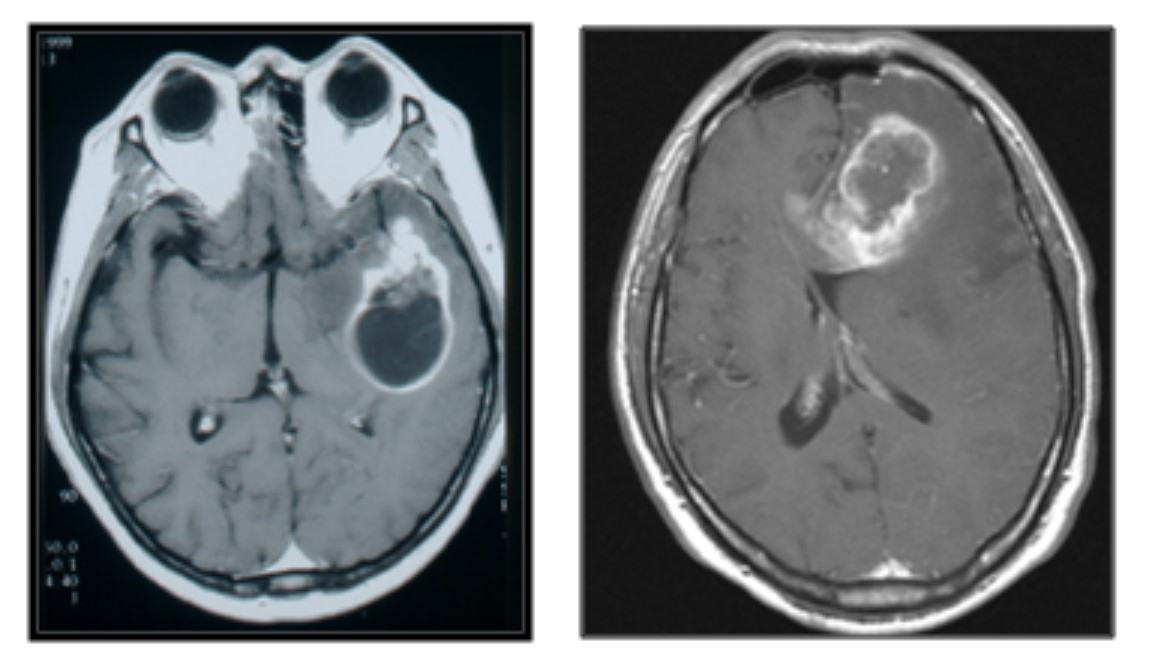

뇌종양 진단의 기본은 MRI 검사다. 이는 뇌종양이 의심될 때뿐만 아니라, 수술 전후 종양의 상태 관찰을 위해 자주 사용된다. 검사에서는 종양 부위를 선명하게 확인할 수 있도록 정맥 조영제를 투여한다.

뇌종양은 조직학적 특성에 따라 '양성'과 '악성'으로 나눈다. '양성 뇌종양'은 성장 속도가 1년에 2㎜ 미만으로 느리다. 주변 부위와 비교적 명확히 구분되기 때문에 수술을 통한 완치 가능성도 높다. 종양의 크기·위치에 따라 일상생활이 불편할 수 있어도, 5년 생존율이 90% 이상일 만큼 생명에 거의 지장이 없다. 따라서 별다른 증상이 없는 경우 경과 관찰만 하며, 증상이 있거나 주기적으로 MRI(자기공명영상)를 촬영하며 관찰하다가 성장 속도가 일반적인 경우보다 빠르다고 판단될 때 치료를 고려해도 늦지 않다.

'악성 뇌종양'은 진행이 빠르고, 성장하면서 뇌 조직을 침범하는 경향을 보인다. 뇌교종이 대표적이다. 뇌교종은 뇌신경세포를 지지하는 교세포에서 발생하며, 절반 이상이 악성이다. 양성 뇌교종도 시간이 지나면서 악성화되는 경우가 많다. 뇌교종이 발견되면 일부 예외적인 경우를 제외하고, 대부분 증상이 없더라도 치료가 필수적이다.